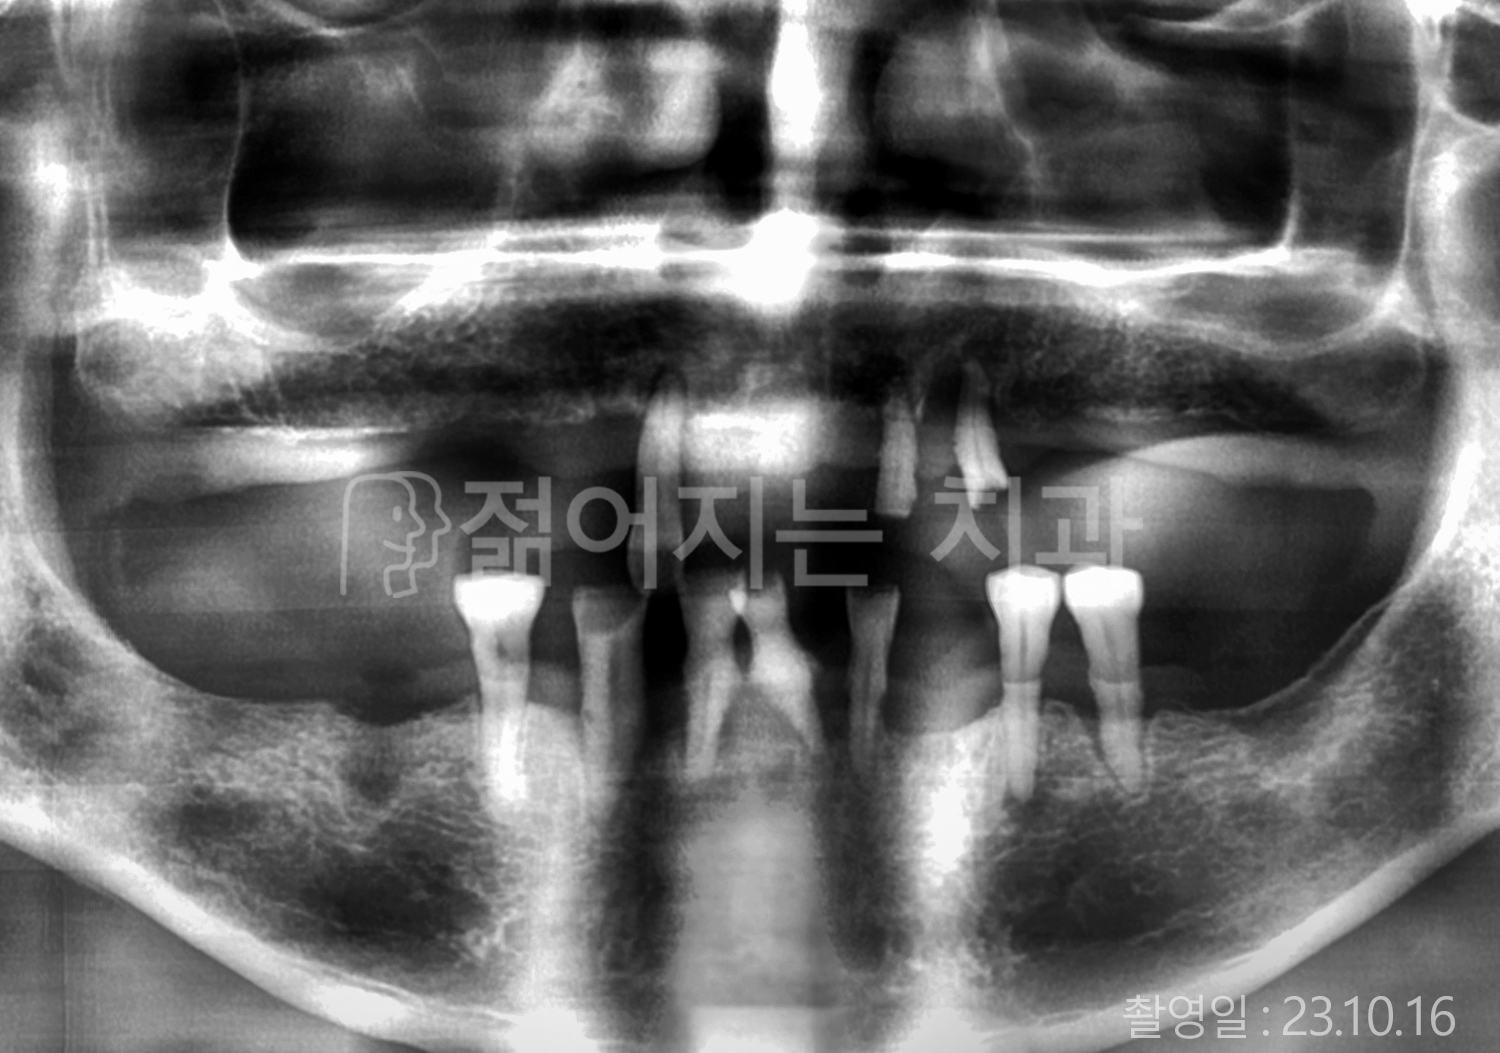

• 70대 고혈압, 당뇨 전체치아 10개 이상 임플란트

• 50대 고혈압, 당뇨 전체치아 10개 이상 임플란트

• 60대 고혈압, 당뇨 전체치아 10개 이상 임플란트

• 50대 전체치아 10개 이상 임플란트

• 70대 당뇨 전체치아 10개 이상 임플란트

• 80대 전체치아 10개 이상 임플란트

• 40대 전체치아 10개 이상 임플란트

• 60대 고협압, 고지혈증 전체치아 10개 이상 임플란트

• 60대 전체치아 10개 이상 임플란트